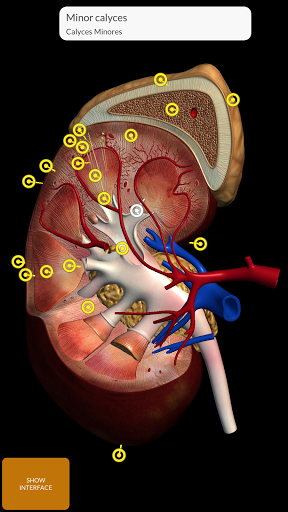

"Anatomy 3D Atlas" cho phép bạn nghiên cứu giải phẫu người theo cách dễ dàng và tương tác.

Thông qua giao diện đơn giản và trực quan, bạn có thể quan sát mọi cấu trúc giải phẫu từ mọi góc độ.

Các mô hình giải phẫu 3D đặc biệt chi tiết và có kết cấu lên đến độ phân giải 4k.

Việc phân chia theo vùng và chế độ xem được xác định trước giúp quan sát và nghiên cứu các bộ phận hoặc nhóm hệ thống riêng lẻ và mối quan hệ giữa các cơ quan khác nhau.

• Hệ thống tiêu hóa • Hệ thống tiết niệu sinh

dục (nam và nữ)

• Bằng cách chọn một mô hình hoặc một ghim, thuật ngữ giải phẫu liên quan sẽ hiển thị

• Các thuật ngữ giải phẫu có thể được hiển thị bằng hai ngôn ngữ cùng lúc